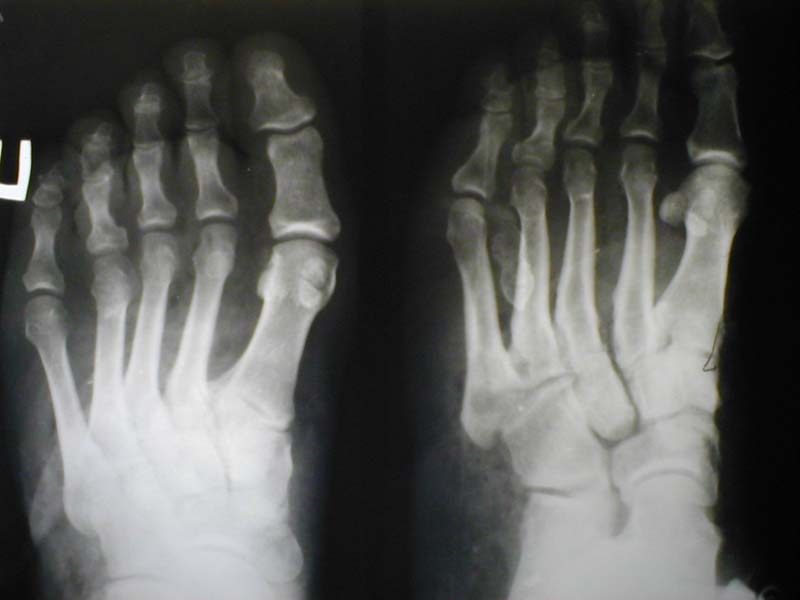

Мужчина, 48лет. Производственная травма (на стопу упал груз весом 2 тонны+химический ожог щелочью).

Диагноз: комбинированная травма правой стопы, обширная рвано-скальпированная рана, химический ожог II ст. до 1% поверхности тела, закрытый перелом ладьевидной и I клиновидной костей.

Фото 1